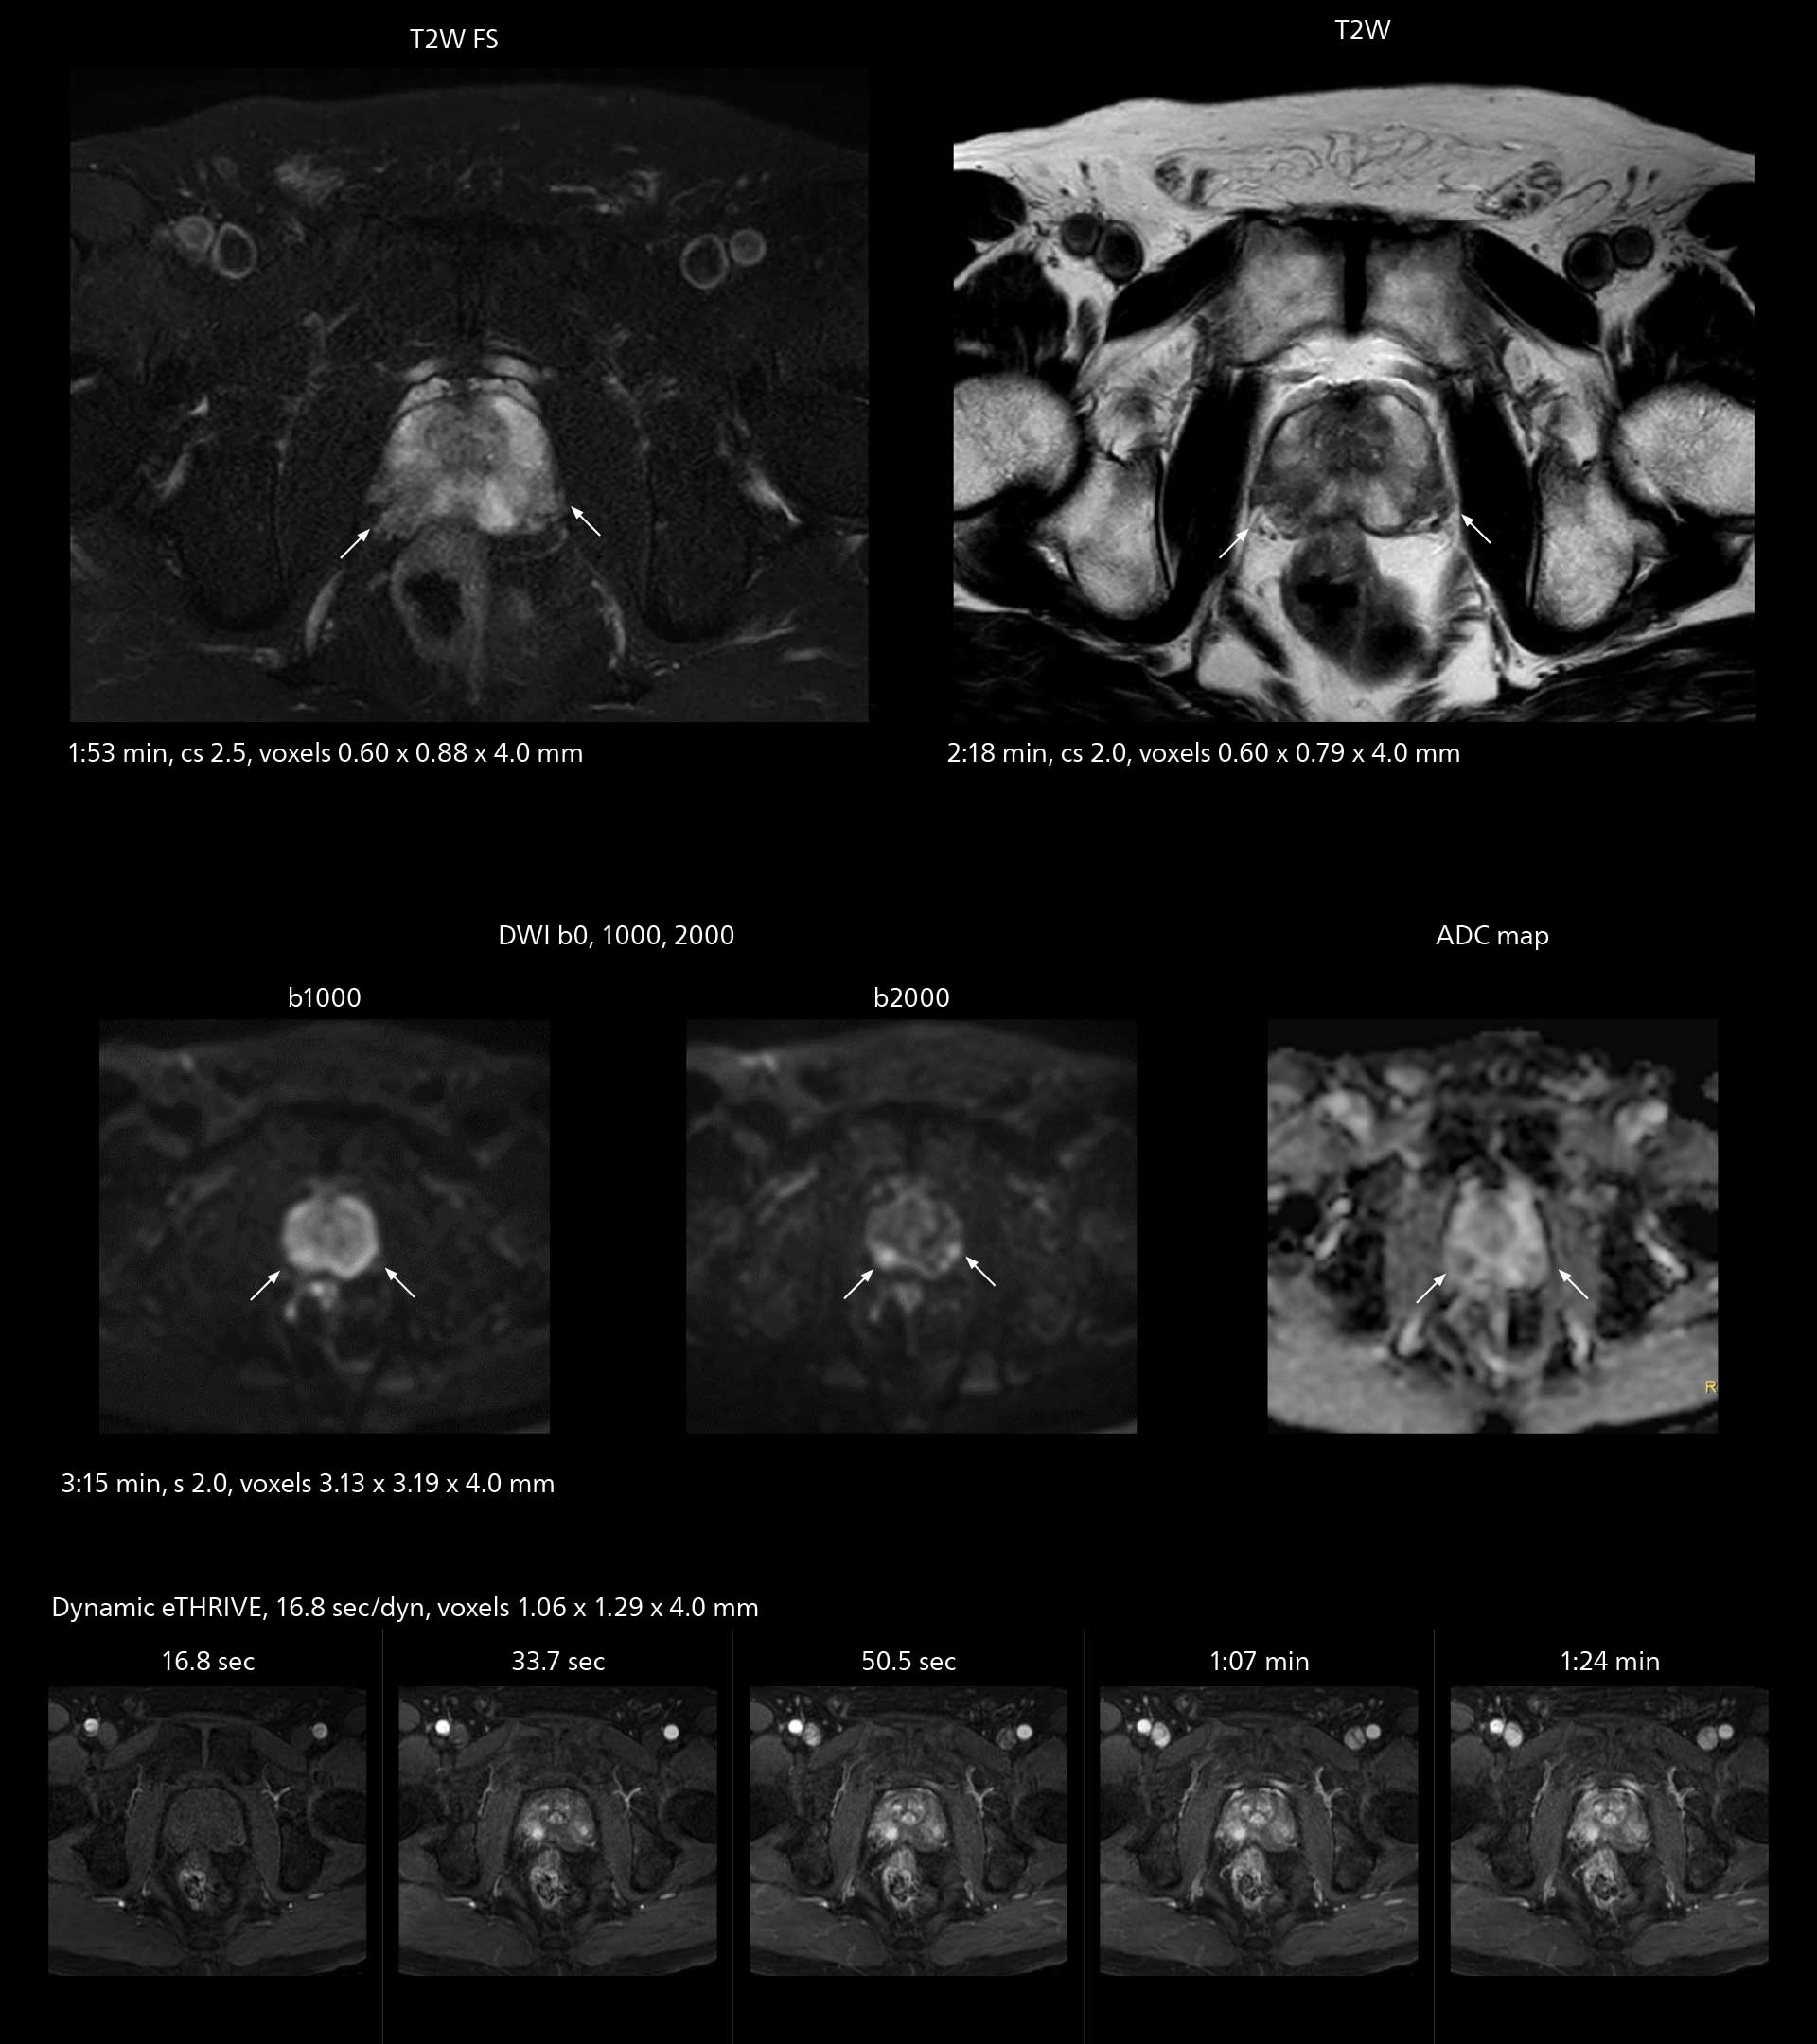

The high performance of the Vega HP gradients is particularly impressive in DWI. “The Vega HP gradients enable us to scan faster and use b-values as high as 2000, for example in prostate DWI and in DWIBS, which provides image quality that is remarkably improved over the previous system and we are able to more easily see lesions.”

Examples of prostate imaging showing faster scan times and improved resolution illustrate the power of SmartPath to Elition X in this case of prostate cancer with PI-RADS score 4.